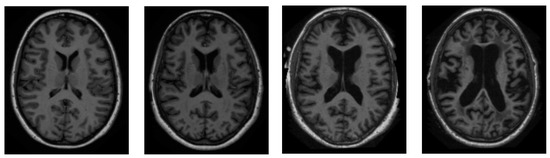

We sourced all of our information from the ADNI dataset [46]. ADNI is an invaluable resource for researchers [47]. A total of 416 people were included in this cross-sectional dataset. The ages of these participants range from 18 to 96 years. Three or four independent T1-weighted MRI scans are acquired in a single session for each subject. The sample images from the ADNI dataset have been presented in Figure 2.

Figure 2.

Sample pictures of an AD patient from the ADNI dataset.

Both sexes are represented, and everyone is dominantly right-handed. From very mild to moderate AD, 100 of the 416 subjects aged 60+ have been diagnosed. A reliability data set, with images from the follow-up appointment within 90 days, is also included for 20 people without dementia.